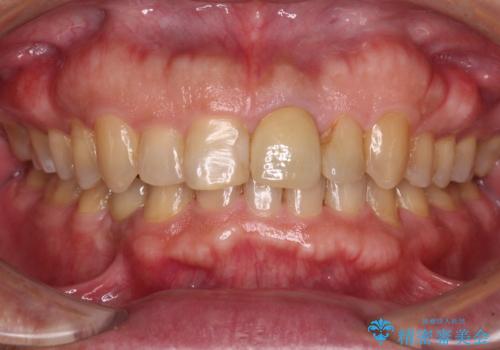

根管治療中の転院 奥歯のオールセラミック治療

根管治療を実施した後、フルジルコニアクラウンに補綴することとしました。

前医での処置後、治療前には気にならなかった痛み続いていたようですが、当院での処置後は痛みが徐々に引いていき、治療から半年が経過した時点では全く違和感も感じなくなりました。

根管治療後のクラウンも、まるでもとの自分の歯のように自然な仕上がりとなり、患者様には大変満足していただけました。